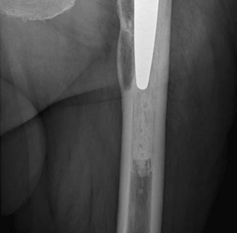

Challenges and solutions: Access to the compo-nents—extensile posterior approach and extended trochanteric osteotomy. Filling acetabular defect—impaction bone grafting, trabecular metal augment, and trabecular metal shell. Filling femoral defect—modular conical diaphyseal fitting stem

4. Femur—since the patient had a long-stem cemented femoral component, we elected to perform an extended trochanteric osteotomy to gain access to the cement mantle and to aid in the extraction of the femoral component. We also elected to use a trochanteric plate with several cerclage cables and an allograft strut to augment stability for the revision femoral component. A modular femoral revision component that gave primary diaphyseal fixation was chosen due to severe proximal femoral bone loss secondary to osteolysis.